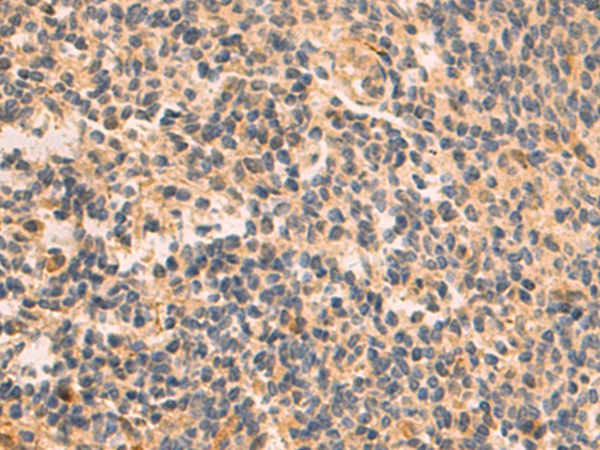

分类: 科研抗体货号: P10581别名: PAL应用: WB,IHC反应种属: Human